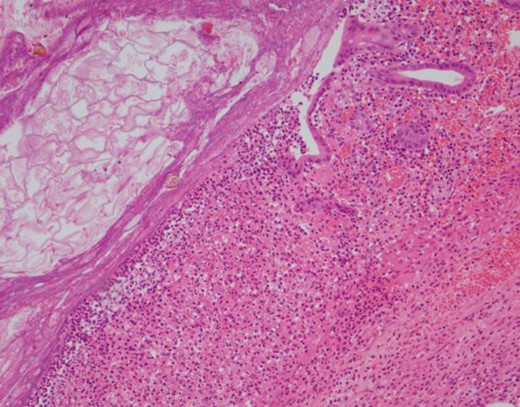

During the exploratory laparotomy, the segment of small bowel with the inflammatory phlegmon was noted and withdrawn from the surgical site for inspection. An isolated segment of bowel measuring ~20 cm was resected between and a side-to-side functional and end anastomosis was created. The surgical findings included a solitary diverticulum at the mesenteric aspect of the bowel with marked erythema, induration and slight exudate at the proximal jejunum. There was no evidence of diverticular perforation. Pathology revealed the serosal surface of the jejunum was notable for a 2.5 cm region of protrusion associated with congestion, exudation and possible hemorrhage; when the resected segment of small bowel was opened, there was a prominent fecal filled diverticulum corresponding to the focus of serosal protrusion (Figs 2–4).

H&E 100× image demonstrating an area of ulceration in the diverticulum with fibrinopurulent exudates occupying most of the right side of the image and food debris in the lumen at the upper left.